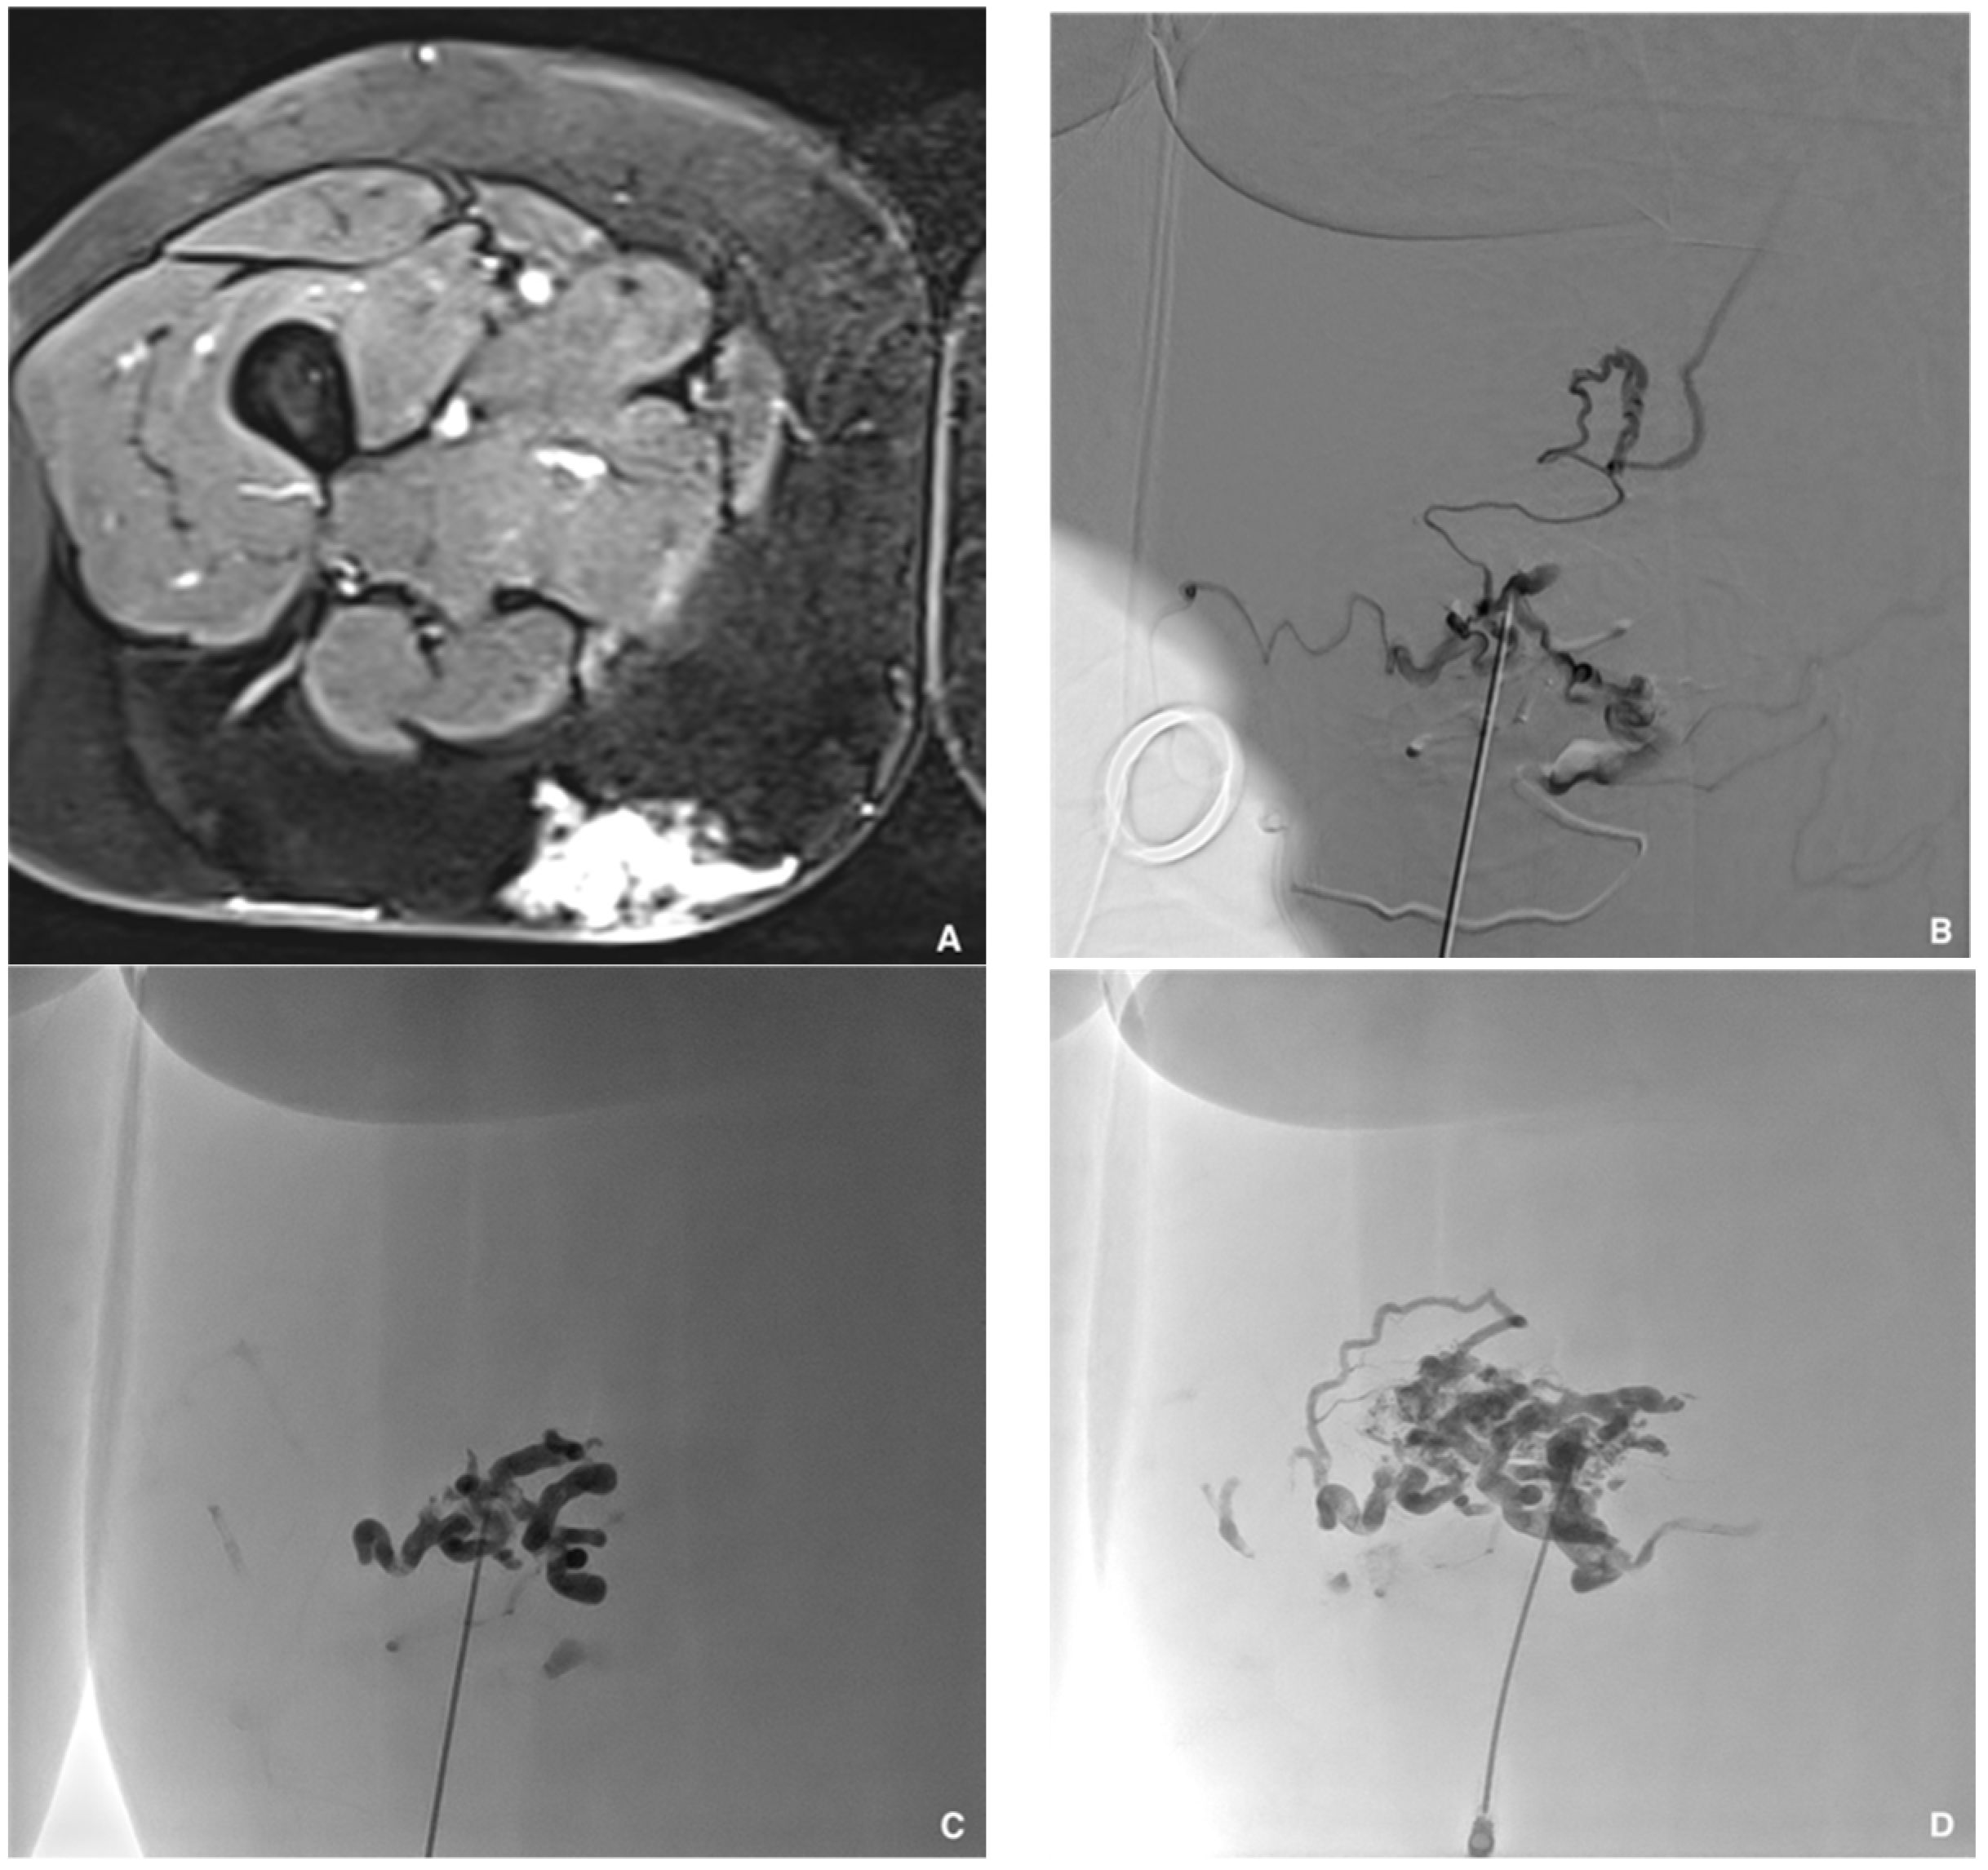

Figure 6. Prophylactic selective embolization of a large angiomyolipoma of the right kidney. (A) Angiography shows two feeding arteries to the angiomylipoma which is hypervascular. (B) Final control after selective and fast embolization of the two arterial branches with a Glubran®2/Lipiodol® mixture of a 1:6 ratio. (C) Computed tomography scan at day 14 showing lipiodol uptake by the angiomyolipoma which is totally devascularized.